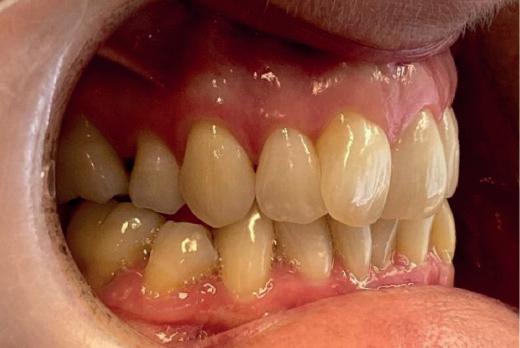

EthOss® is a 100% synthetic bone graft material for dental implant surgery. With no risk of cross-contamination, EthOss® works with the body’s healing process by creating a calciumrich environment and is completely absorbed.